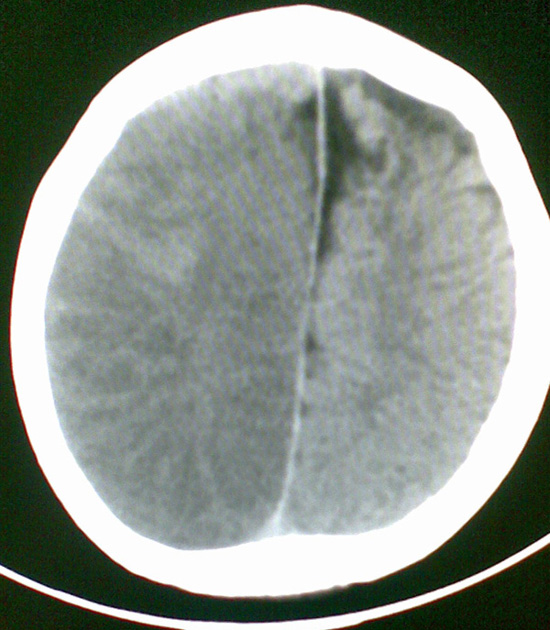

男4岁,反复抽搐多年,今早再次大抽搐,伴昏迷

考虑---右侧大脑半球脑梗死

右侧大脑半球密度减低,脑组织肿胀,占位?建议增强。

考虑脑梗塞. kaolv 血管病变---烟雾病可能

1)右侧大脑半球大面积脑梗塞。2)双侧额叶脑软化灶。3)脑萎缩。

建议:必要时行dsa检查排除烟雾病可能。

右侧半球梗塞,多发软化灶,考虑血管畸形继发,进一步检查。

右侧大脑半球大面积脑梗塞。双侧额叶脑软化灶。考虑血管畸形继发,建议进一步检查。

1右侧大面积脑梗死2左侧额颞部软化灶。